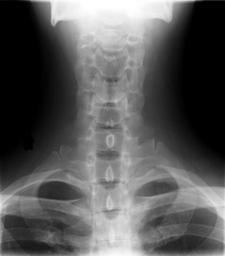

MAKE A MEME View Large Image Cervical Xray Lower AP View.jpg en X-ray of cervical spine neck AP front view This series of x-rays were part of pre-surgical evaluation to help identify spinal instability Patient is a 37 year old male with a history of multiple neck ...

Keywords: Cervical Xray Lower AP View.jpg en X-ray of cervical spine neck AP front view This series of x-rays were part of pre-surgical evaluation to help identify spinal instability Patient is a 37 year old male with a history of multiple neck traumas with pain and muscle spasms and dental implant in lower jaw Excerpt from radiologist's report FINDINGS Five views of the cervical spine including flexion and extension were performed There is no evidence of fracture bone destruction or malalignment There are degenerative bone and is changes at C5-6 There is no evidence of cervical instability on the flexion and extension views The facet joints are well aligned Bony spurring is narrowing the C5-6 neural foramina bilaterally IMPRESSION Degenerative changes at C5-6 No evidence of instability Ragioagraphie aux raysons X du rachis cervical cou AP vue avant Cette série de radiographies faisaient partie de l'évaluation pré-chirurgicale pour aider à identifier une instabilité vertébrale Le patient est un homme de 37 ans ayant des antécédents de traumatismes multiples cou avec des spasmes et des douleurs musculaires et implant dentaire à la mâchoire inférieure Extrait du rapport du radiologiste RÉSULTATS Cinq vues de la partie cervicale de la colonne vertébrale ont été faites dont en flexion et en extension Il n'y a pas de signe de fracture de destruction osseuse ni de défaut d'alignement On observe un phénomène de gégénérescence osseuse des changements en C5-6 Il n'existe aucune preuve de l'instabilité du cou sur les radios montrant la flexion et l'extension Les facettes articulaires sont bien alignés Bony spurring is narrowing the C5-6 neural foramina bilaterally IMPRESSION Changements dégénératifs eu C5-6 Aucune preuve d'instabilité own medical image work for hire Stillwaterising 2010-04 File Cervical Xray Extension jpg File Cervical Xray Extension view jpg File Cervical Xray Lateral View jpg Magnification 0 4x converted from lossy DICOM file Cc-zero Anteroposterior X-rays of the neck Dicom Human anatomy cervical vertebrae